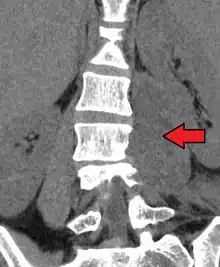

Psoas abscess is a collection of pus in the iliopsoas muscle compartment.[1][2] It can be classified into primary psoas abscess (caused by hematogenous or lymphatic spread of a pathogen) and secondary psoas abscess (resulting from contiguous spread from an adjacent infectious focus).[2]

Psoas abscess may be caused by lumbar tuberculosis. Owing to the proximal attachments of the iliopsoas, such an abscess may drain inferiorly into the upper medial thigh and present as a swelling in the region. The sheath of the muscle arises from the lumbar vertebrae and the intervertebral discs between the vertebrae. The disc is more susceptible to infection, from tuberculosis and Salmonella discitis. The infection can spread into the psoas muscle sheath.[3]

Paraspinal abscess in the psoas muscle